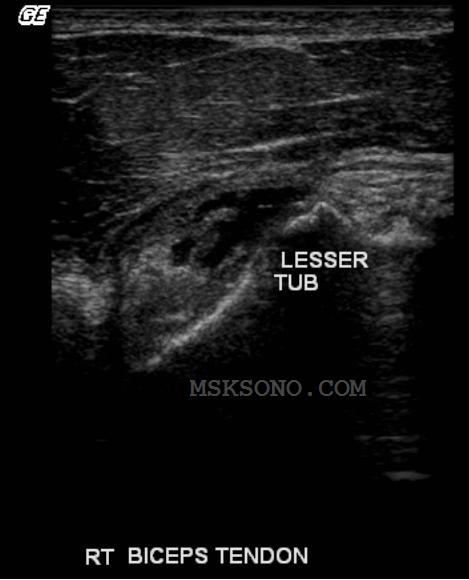

Subscapularis image

shows retraction with

anechoic fluid in place of

the insertion to the

Lesser Tuberocity.

Further

evaluation of the

Lesser Tuberocity

reveals an

avulsion.